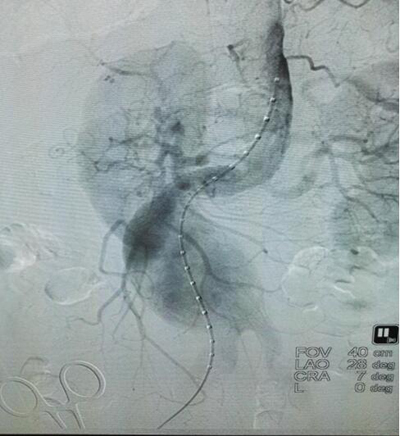

(患者杨某术前影像图)

患者杨某、男性、71岁,以“发现主动脉瘤五天”之主诉入院。5天前患者在当地医院行MR提示:腹主动脉分叉上方类圆形异常信号影,考虑“腹主动脉瘤”。既往有高血压病史5年,最高血压160/100mmHg,心电图显示陈旧性心梗,心脏彩超,冠心病改变,三尖瓣反流、肺动脉瓣反流。我院CT结果,腹主动脉下段至髂总动脉管腔呈瘤样扩张。结合患者体征病史以及各项检查结果,主管医生马建仓教授很快做出了诊断,制定出针对该患者的治疗方案,尽快进行血管介入手术治疗。进行了充足的术前准备后,为患者在局麻下行介入手术治疗,主动脉支架植入术。